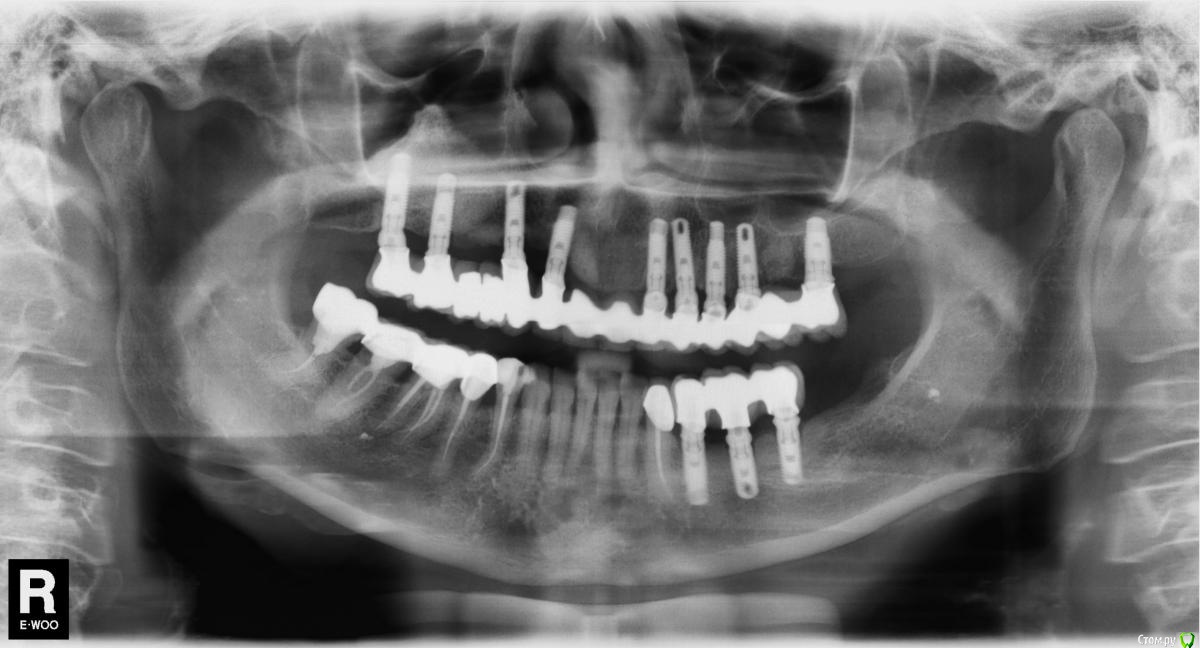

Dantist55 Опубликовано 3 марта, 2016 Поделиться Опубликовано 3 марта, 2016 Коллеги нужна помощь в определении системы. Ссылка на комментарий